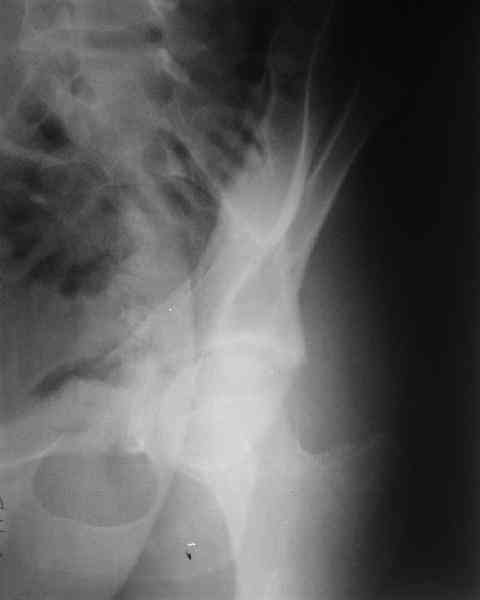

The last two images from the 3-D CT scan certainly makes the fracture look worse than the plan radiographs.

The joint is non-concentric as the head appears to be either "following the caudal segment", or the dome component is displaced from the tethered head... or so it seems... and he's young... so, many fracture surgeons would recommend reduction and fixation.

While not claiming to have the best 3D brain around, it appears to me from the limited images available, that the caudal segment is stable from the symphysis to the SI joint on the fracture side. I would love to see the rest of the transverse CT images to see where the fracture line actually exits posteriorly on both the inner and outer tables of the ilium. In my hands,

Some more images. Does it help to guess which part of the acetabulum is displaced?

Normal appearing SI joints and a healed posterior column limb... my bet's on caudal segment displacement.